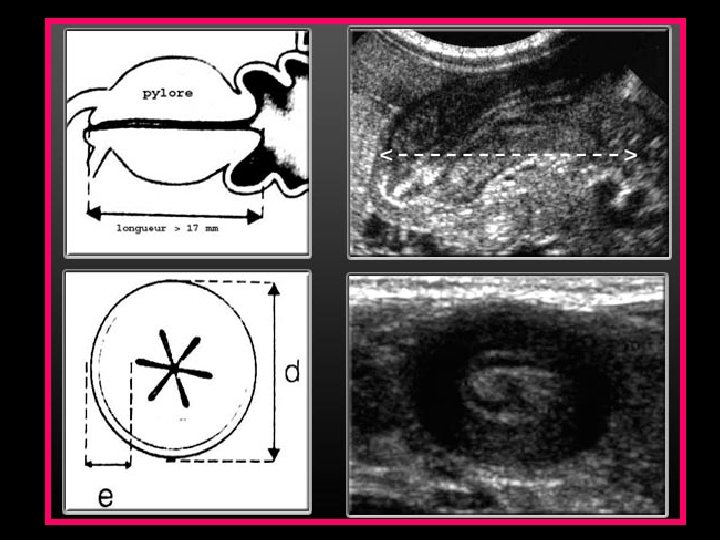

ECHOGRAPHIE ABDOMINALE • Maître examen +++ • Diagnostic précoce • Confirme le diagnostic : - longueur du pylore > 19 mm - largeur > 13 mm - épaisseur de la paroi musculaire > 4 mm • Image en cocarde en coupe transversale et en sandwich en longitudinale